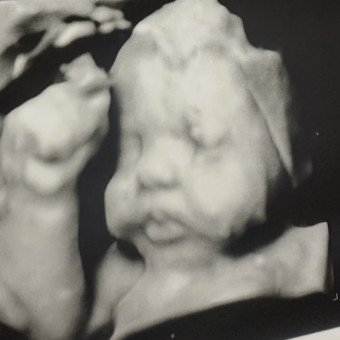

Ashlyn & Cooper Meurer

Midland, TX

May 5, 2026

We can’t wait for the arrival of our Babygirl. Thank you friends and family for supporting us in this time. May God Bless you!